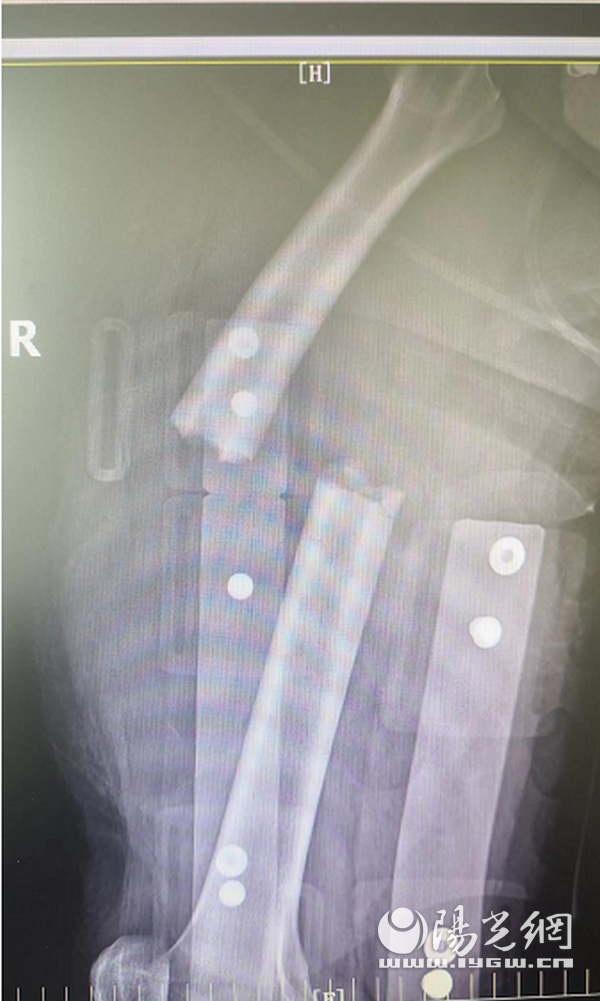

为了尽快挽救患者生命、保全肢体,在对伤口进行冲洗消毒和扩创探查后,张俊荣根据其病情带领团队分两组同时实施:一组进行清创,去除失活的脂肪和肌肉组织,复位固定股骨干骨折;另一组则切取患肢对侧(左侧)的大隐静脉30厘米,然后将其分成两段,在显微镜下桥接移植给右股动脉约15厘米,右股静脉约10厘米。

经过惊心动魄的5个多小时,移植的静脉、动脉成功吻合,血管血流通畅、搏动有力,小腿远端血运随即红润起来。随后,张俊荣还带领团队还为张强进行了右大腿皮肤脱套伤返取皮植皮负压吸引术、小腿筋膜间室切开减压负压吸引术、右上臂皮肤脱套伤切开探查负压吸引术等,以最大限度保障手术效果。